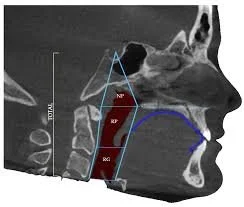

Great orthodontic care means looking at the bigger picture. Dr. Yoon evaluates bite function, everyday movement, and facial balance to create results that are comfortable, stable, and designed to last.

Orthodontic treatment can affect jaw joints. Dr. Yoon plans carefully to support smooth movement and reduce stress on the TMJ.

Jaw and tooth position can influence how you breathe. When needed, breathing patterns are considered to support balanced oral function.